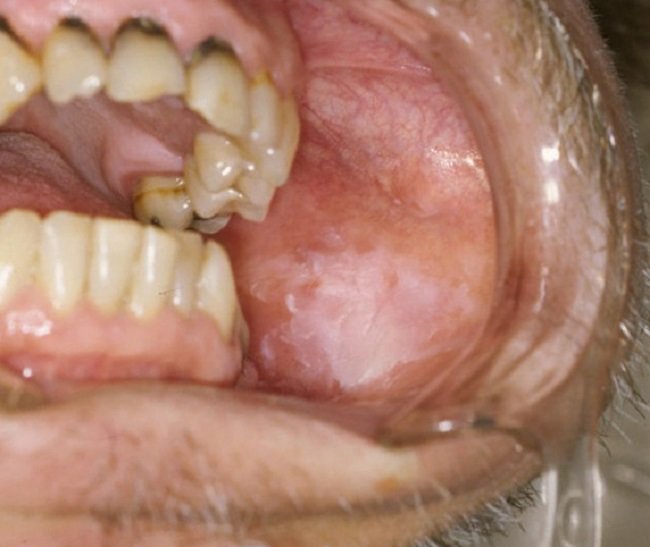

Leukoplakia ditandai dengan timbulnya bercak di dalam mulut. Bercak ini dapat berkembang perlahan dalam beberapa minggu atau bulan.

Bercak pada leukoplakia biasa umumnya timbul pada lidah, sebelah dalam pipi, langit-langit mulut, serta di bawah lidah (dasar mulut). Sementara pada leukoplakia berambut, bercak umumnya muncul di bagian samping lidah.

Adapun ciri bercak pada leukoplakia antara lain:

Meski tidak menimbulkan nyeri, bercak ini bisa sensitif terhadap panas, makanan pedas, atau sentuhan.